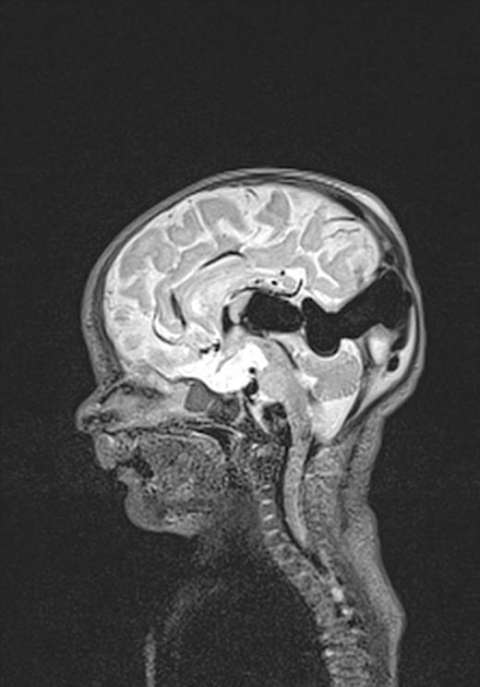

- Cranial MRI and/or CT Scan (performed with or without contrast medium) - Cranial imaging can assist in confirming the diagnosis of VGAM and determine whether hydrocephalus is present, as well. Non invasive MR angiography can provide very useful information for treatment planning.